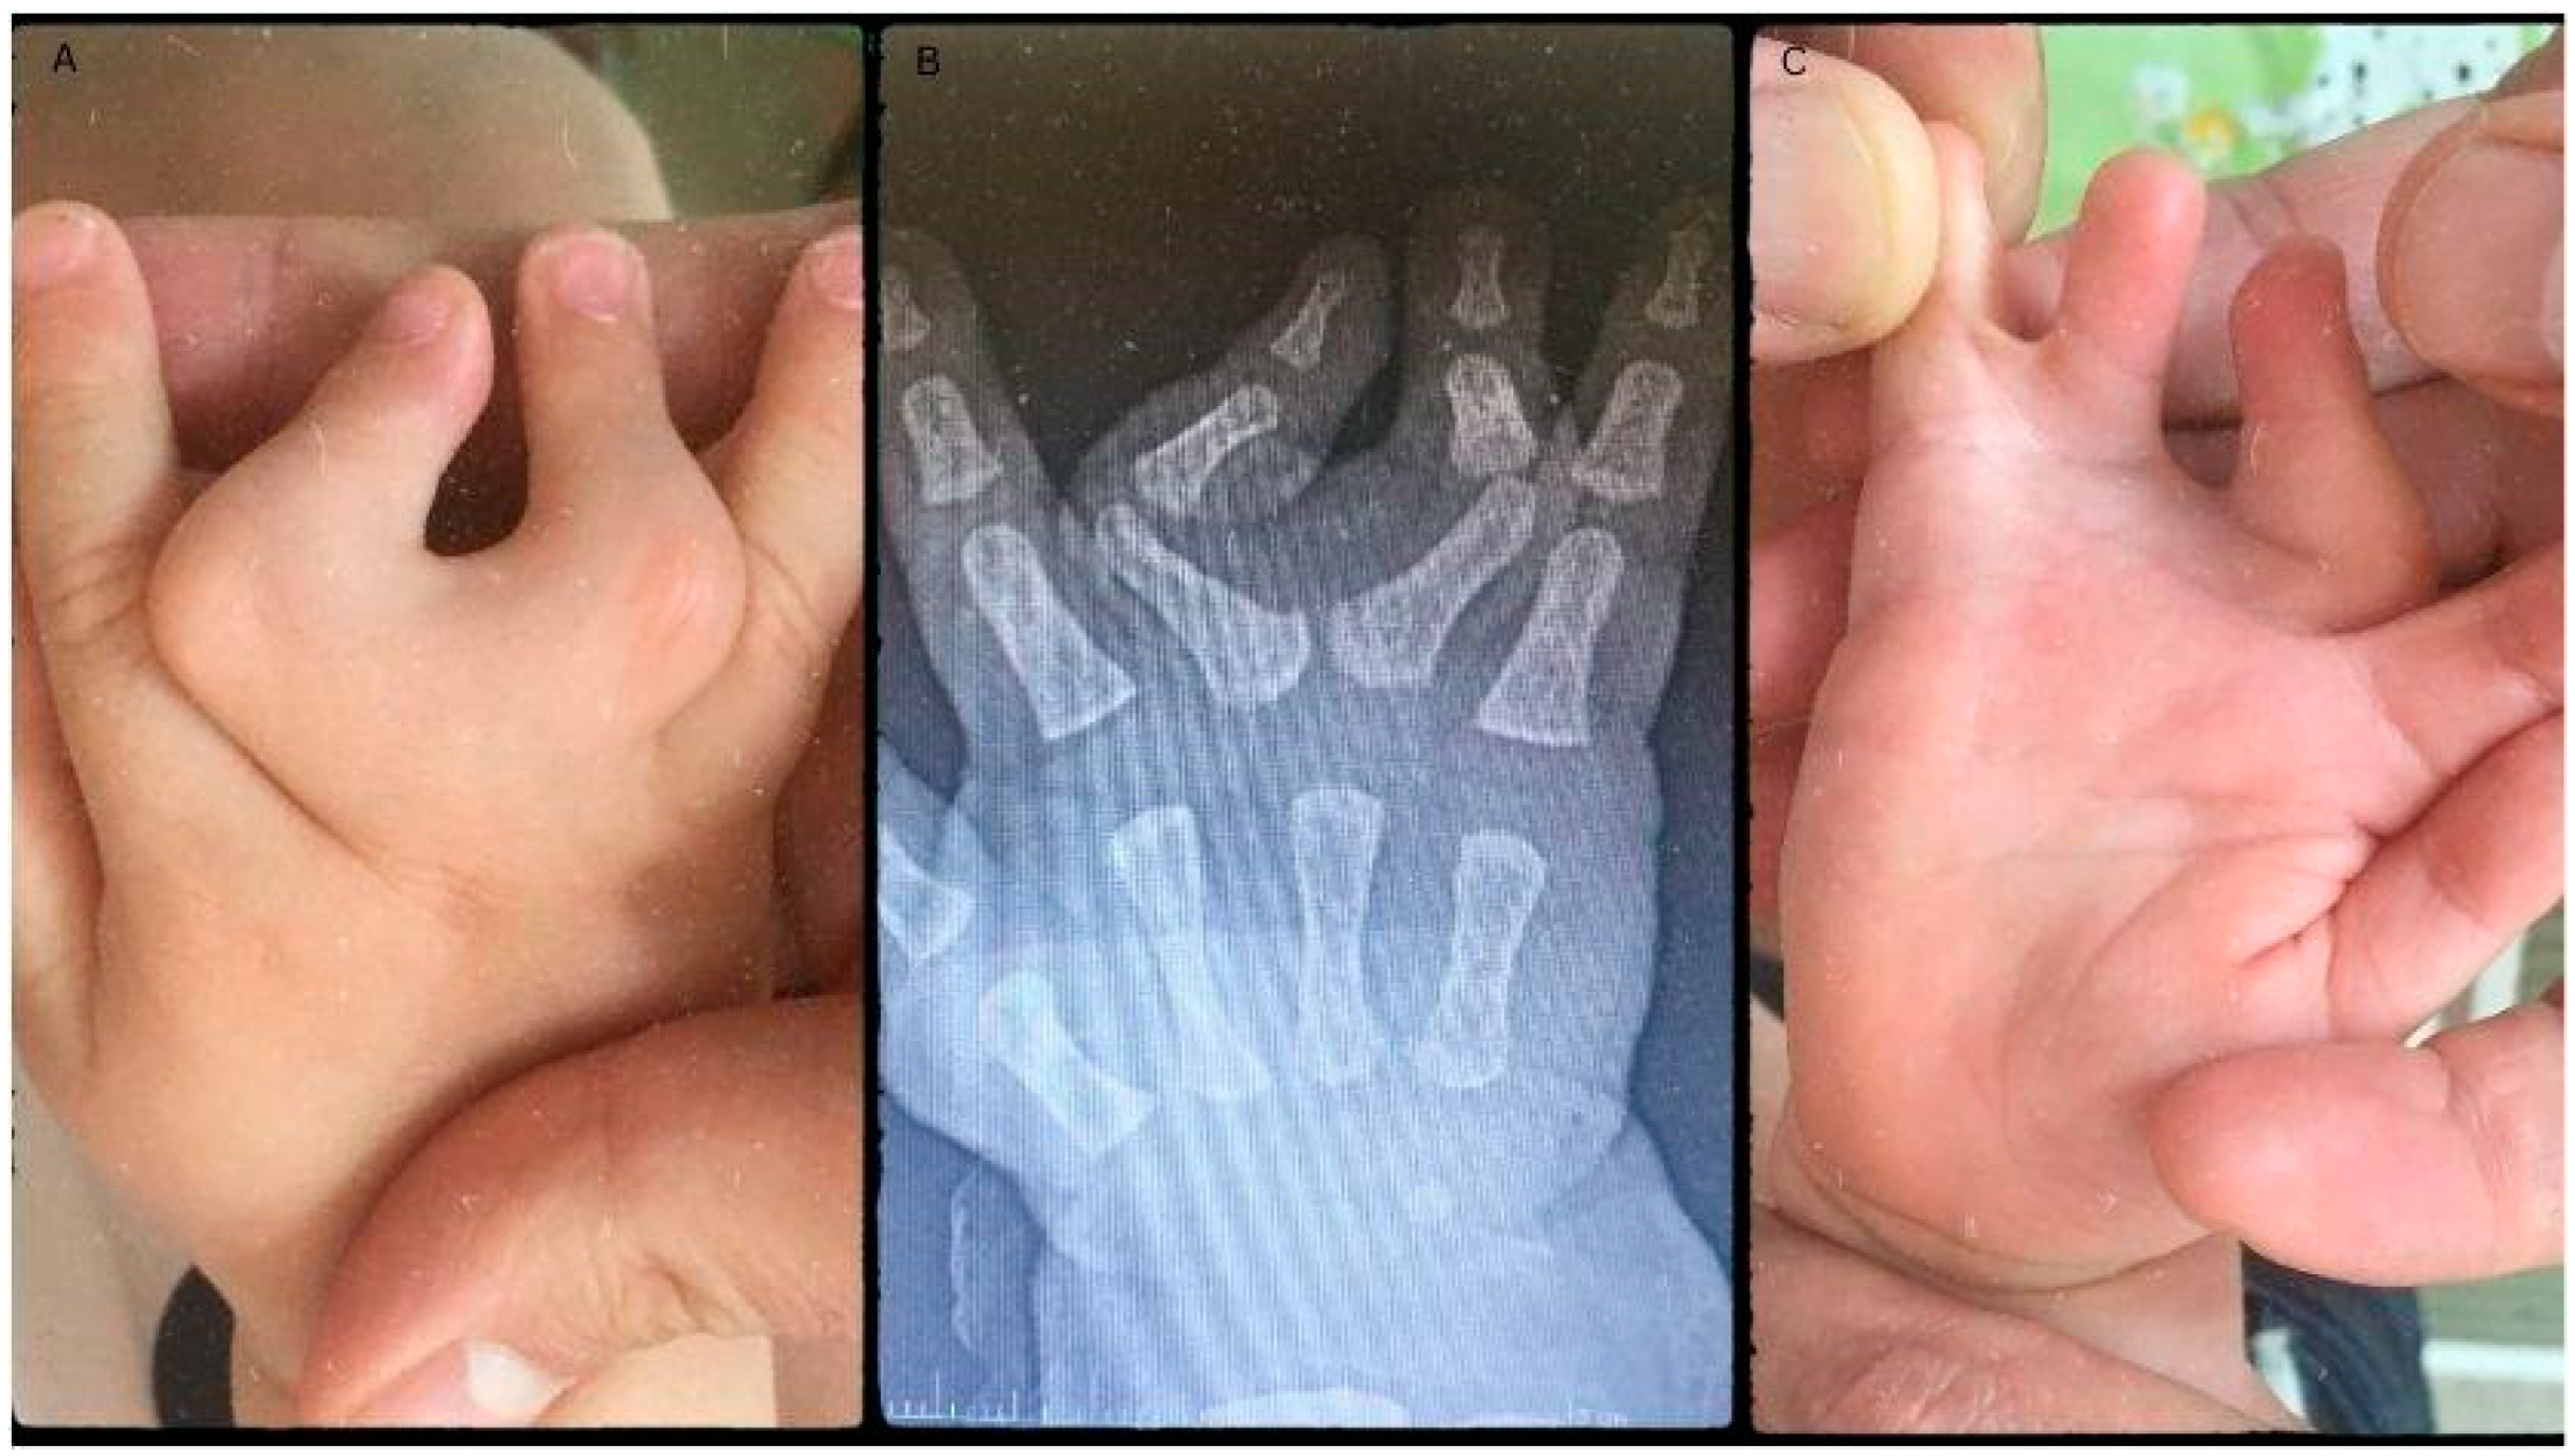

A girl born in June of 2019 was diagnosed with congenital malformation of the right hand at birth — affecting the right middle, ring and little fingers, respectively. Upon physical examination, the III. digit deviates from its origin at the metacarpophalangeal joint (MCP) radially approximately 45 degrees, while the IV. finger deviates to the ulnar side 45 degrees from the MCP joint. Clinodactyly is apparent when looking at the proximal-interphalangeal (PIP) joints of the III and IV. finger, as they are positioned in a close to 90-degree deviation. Between the IV and V., finger webbing was visible, resembling a plate, adding to the syndactyly component of the malformation (Figure 1A). The fingers' PIP and distal interphalangeal (DIP) joints were movable; however, passive flexion and extension were restricted. The passive flexion of the MCP was close to 90 degrees, while extension was limited. Radiological evaluation revealed a common metacarpal of the III and IV. finger (Figure 1B). Altogether, there were only four metacarpal bones in the patient's hand. The common MCP joint was fused with the proximal phalanxes of the middle and ring fingers. The plate acquired a deviated position which led to the angular displacement of the fingers. The PIP joints’ clinodactyly was apparent as the large degree of deviation speaks for itself. In this case, the middle finger’s deviation was a close 90-degree deviation towards the ulnar side, while the ring finger deviated radially approximately 40 degrees with the interdigital webbing of the little and ring fingers (Figure 1C). Functionality was restricted both actively and passively, with some flexion present. Grasp and pinch function was decreased as the child could not hold items in their palm faced down. When grabbing items the child used the index finger and thumb to hold onto the object. These findings formed the diagnosis of clino-syndactyly of the III and IV. finger’s base and PIP joints, with incomplete cutaneous syndactyly of the IV and V. digits, paired with metacarpal aplasia of the IV. metacarpal bone.

Figure 1. Pre-operative pictures depicting the malformations (A and C). The radiograph shows the degree of deviation and the missing metacarpal (B).